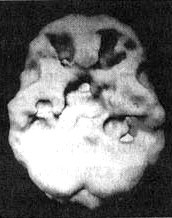

Мозг Роба. Алкогольная, кокаиновая и метамфетаминовая зависимость

Трехмерное изображение поверхности, вид сверху. Обратите внимание на многочисленные «провалы» активности и сморщенный вид мозга в то время, когда Роб злоупотреблял этими веществами.